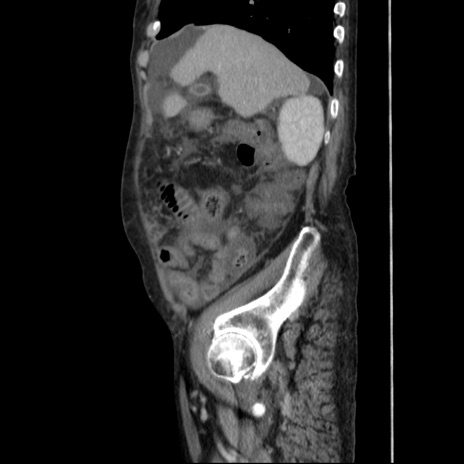

症例31(矢状断像)

【症例】80歳代 女性

【主訴】腹部膨満感

【現病歴】他院にて肝硬変にてフォロー中。1週間前から便秘、腹部膨満感、臍部腫瘤あり受診となる。

【既往歴】肝硬変

【身体所見】腹部膨隆あり、皮膚変化なし、疼痛なし。

【データ】WBC 4600、CRP 0.25